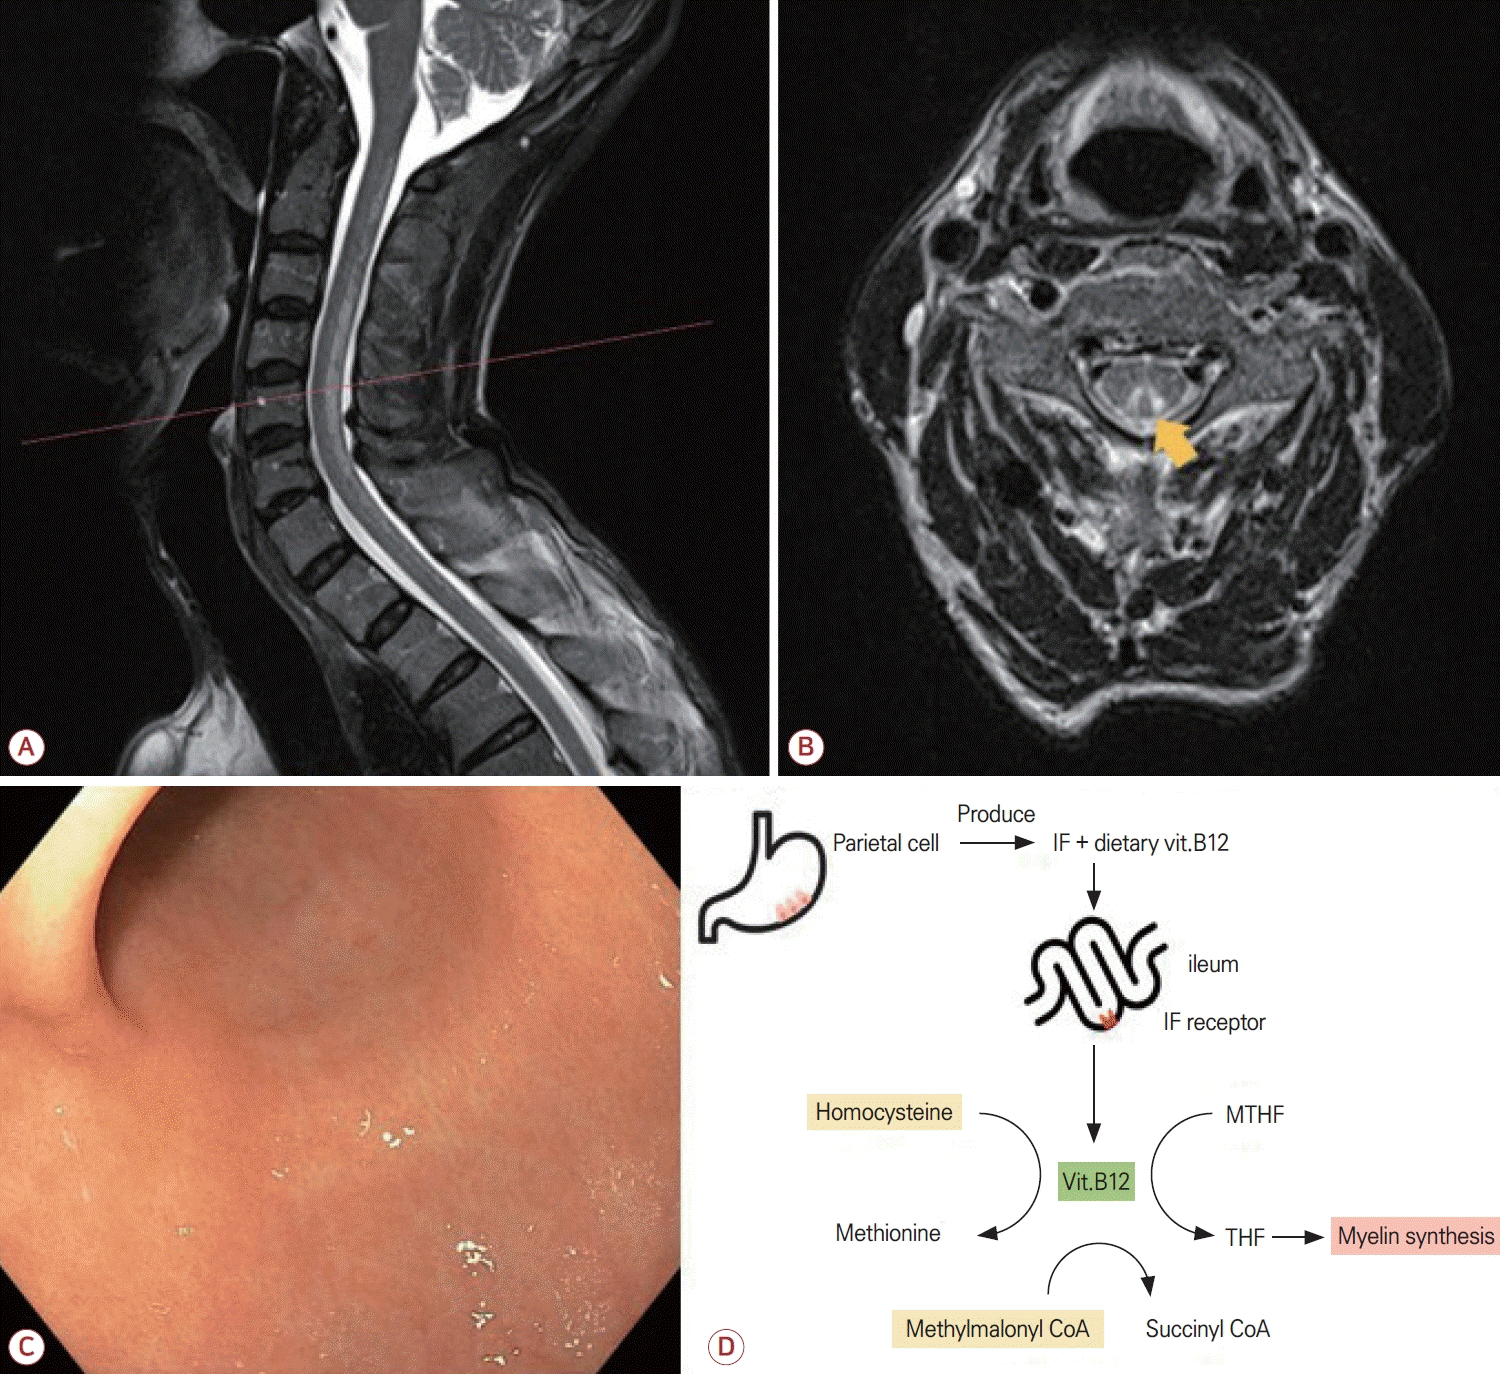

몸감각유발전위(somatosensory evoked potential, SSEP) 검사에서는 양측 정중신경(median nerve)의 중심전도로 지연이 확인되었고 양측 정강신경(tibial nerve)에서도 전도 이상이 의심되었다. 척수 자기공명영상(magnetic resonance imaging, MRI)에서는 경추 및 흉추의 뒤기둥에 고신호병터가 확인되었고(Fig. A) 가로횡단면에서 뒤집힌 V징후(inverted V sign)가 관찰되었다(Fig. B). 상부위장관내시경에서는 만성 위염 소견만 관찰되었으며(Fig. C) 조직 검사에서도 만성 위염이 확인되었다. 헬리코박터균(Helicobacter pylori)에 대한 중합효소사슬반응(polymerase chain reaction, PCR)은 음성이었고 혈청 가스트린(gastrin)은 575 pg/mL (정상, 13-115)로 상승되어 있었다. 위벽세포항체(anti-parietal cell antibodies)는 음성이었으나 내인자(intrinsic factor, IF)항체는 양성이었다. 위점막 생검에서는 모든 부위에서 만성 위축위염 소견이 보였고 위바닥(fundus)에서는 위오목증식(foveolar hyperplasia)이, 위몸통(mid body)에서는 위오목증식 및 장상피화생(intestinal metaplasia)이 추가적으로 관찰되었다. 소화기내과 협진을 통해 AIG가 고려된다는 답변을 받았으며 신경계 진찰과 영상 및 혈청 검사 소견을 종합하여 AIG로 인한 비타민B12 결핍에 의한 SCD로 진단하였다.

IF는 위의 벽세포에서 분비되는 당단백질로 회장에서 비타민 B12 흡수를 위한 필수적인 역할을 한다. 악성 빈혈에서는 IF 또는 벽세포에 대한 자가항체가 존재하여 비타민B12 흡수를 방해하고 이로 인하여 전신 결핍 상태로 이어진다. 비타민B12는 메싸이오닌 합성 및 수초 유지에 중요한 역할을 하며 결핍되면 메틸화장애, 메틸말론산 축적, 수초 손상이 유발되어 척수의 뒤기둥 및 가쪽기둥에 병터가 발생한다[12]. 이로 인하여 감각실조, 감각이상, 경직 등의 증상이 SCD로 나타난다(Fig. D).

Figure.

(A) Sagittal T2-weighted MRI of the spine showing a longitudinal hyperintense signal predominantly involving the dorsal columns of cervical to upper thoracic cord levels. (B) Axial T2-weighted image at the level indicated in (A) demonstrating inverted V sign (arrow), a hallmark of subacute combined degeneration. (C) Upper gastrointestinal endoscopy showing mild diffuse erythema and mucosal granularity compatible with chronic gastritis, with no overt endoscopic atrophy. (D) Pathophysiological schema linking autoimmune gastritis to vitamin B12-related myelopathy. Gastric parietal cells produce intrinsic factor (IF), which binds dietary vitamin B12 and enables its uptake in the terminal ileum via the IF receptor. Absorbed B12 circulates on transcobalamin and serves as an essential cofactor for methionine synthase and for methylmalonyl-CoA mutase. In autoimmune gastritis, reduced IF-mediated absorption leads to cellular B12 deficiency, resulting in elevated homocysteine and methylmalonic acid and culminating in posterior column demyelination characteristic of subacute combined degeneration. vit.B12; vitamin B12, MTHF; methylenetetrahydrofolate, THF; tetrahydrofolate, MRI; magnetic resonance imaging.